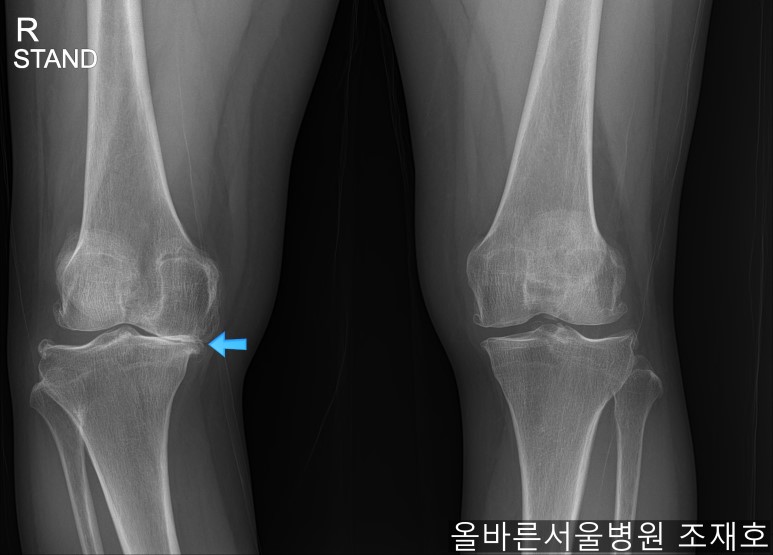

手术后可通过片子看到矫正后的正面样子。

此时内侧稍微分开,开始行走且软骨开始再生,内侧会更加分开。

侧面也矫正成功。